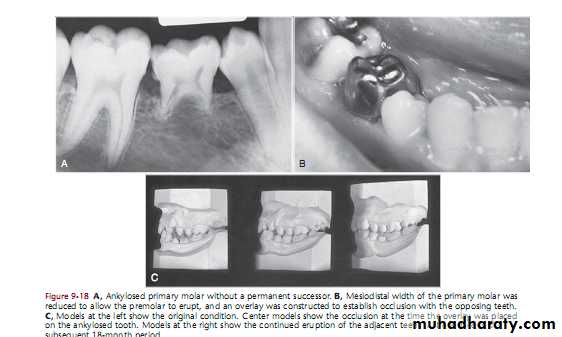

ANKYLOSIS OF PRIMARY MOLARS WITH ABSENCE OF

PERMANENT SUCCESSORSIf missing one tooth or two teeth do onlay

If missing of three or four teeth referred to ortho

If one side or two sides missing permanent toothSystemic factors